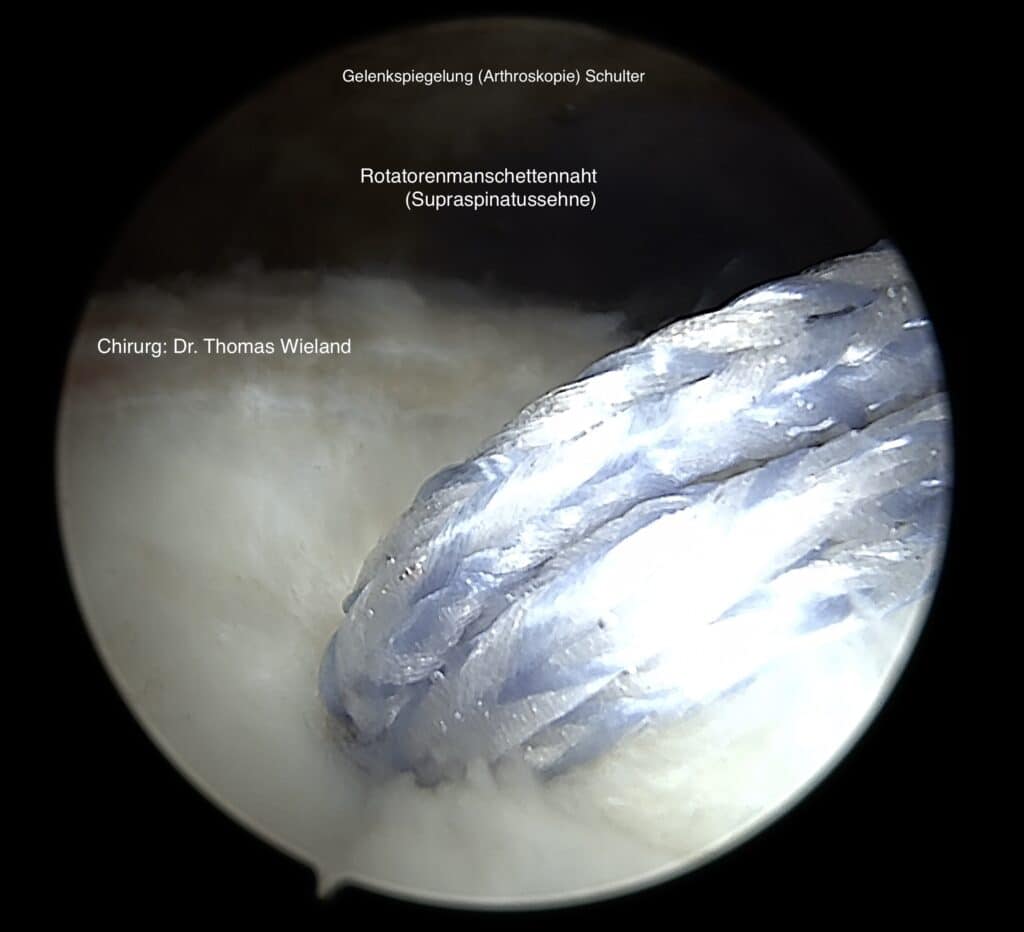

Therapiemöglichkeiten für Schulterverletzungen an der Rotatorenmanschette

Werden kleine Läsionen festgestellt, so können diese zumeist unter fachkundiger Einzelheilgymnastik behandelt werden, denn das erste Ziel zur Behandlung von Schmerzen und Verletzungen an der Schulter ist stets die „Konservative Therapie“. Größere Risse im Bereich der Rotorenmanschette erfordern jedoch häufig eine chirurgische Sanierung.